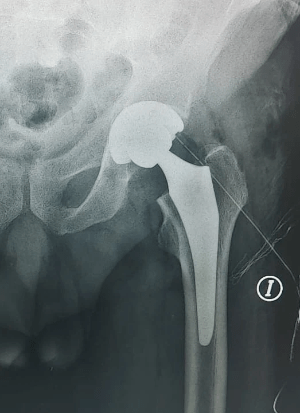

TOTAL HIP REPLACEMENT

We are specialized in the surgical treatment of hip disease. The latest advances in prosthesis surgery are used, using the least invasive techniques that improve both results and recovery after surgery, and also the best and most advanced prosthesis models on the market, at a moderate cost.